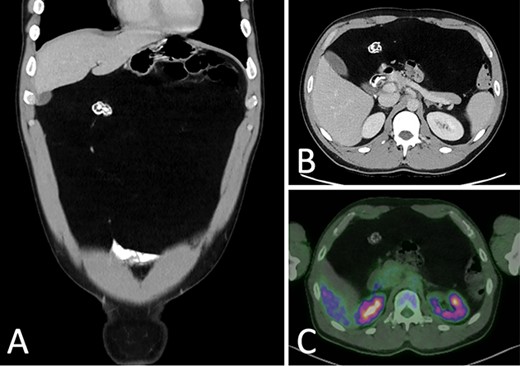

Abdominal ultrasound (US) revealed a well-demarcated, mildly hyperechogenic mass lesion apparently occupying the left lobe of the liver and measuring 6 × 25 × 24 cm. Both contrast-enhanced computed tomography (CT) and magnetic resonance imaging (MRI) demonstrated a well-circumscribed lipomatous mass within the greater omentum, measuring 9 × 24 × 27 cm, without discrete enhancing soft tissue components or local invasive features (Fig. 1). There were several foci of internal coarse calcification on CT corresponding with areas of low T1 and T2 signals and thin peripheral rim enhancement on MRI suggestive of focal fat necrosis. Intra-abdominal mass effect was evident but without acute complications. No metabolically active disease was demonstrated on fluorodeoxyglucose positron emission tomography (FDG-PET) (Fig. 2).

CT portal venous phase (A) coronal slice (B) axial slice demonstrating a focus of coarse calcification and intra-abdominal mass effect; (C) FDG-PET CT axial slice demonstrating a non-metabolically active lesion.